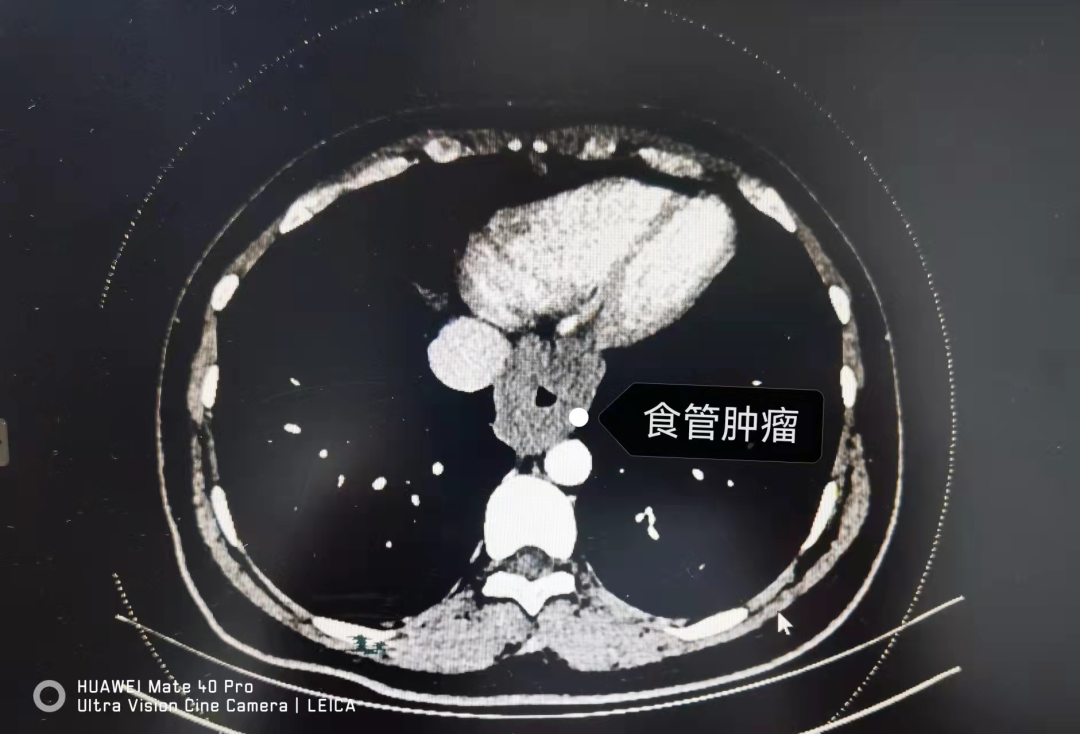

家人感觉不对赶忙带她在当地医院检查,CT发现食管下段异常增粗,当时怀疑是恶性肿瘤,后来又在另一家医院检查胃镜,结果没想到的是,胃镜的镜身根本就无法通过病变的狭窄处。

最终,姚女士来到了河北医大一院胸外二科。经过检查,医生对姚大姐食管下段的肿物有了初步的判断。

在医生的精细操作下,肿瘤完整切除,幸运的是,病理显示,该肿物为良性的平滑肌瘤。

▲从姚大姐体内取出的长达9cm的肿瘤